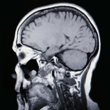

AIDS dementia complex

AIDS dementia complex (ADC), also known as HIV dementia, HIV encephalopathy and HIV-associated dementia, is a common neurologic disorder associated with HIV infection and AIDS. Dementia occurs when neurocognitive impairment is severe enough to interfere... read more